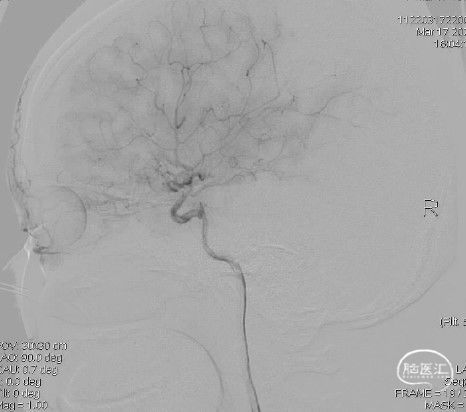

病人乙的影像资料:

造影:右侧颈内动脉末段变细,右侧大脑中动脉M1段分叉前重度狭窄,豆纹动脉增多,右侧大脑前动脉向大脑中动脉分布区代偿供血:

右侧颈内动脉正位:

右侧颈内动脉侧位: